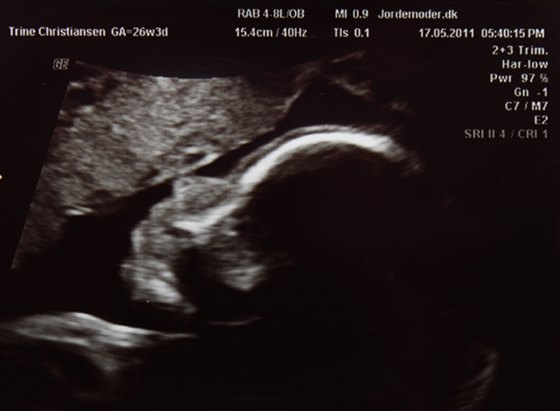

Vi var til en kønscanning i dag

eller lille er måske så eget sagt.. heh.. Der blev selvfølgelig taget lidt forskellig mål og lavet et skøn på vægten, som lyder på Ca. 913g.

Men det hele var bare såå flot. Og så var det jo SUPER dejligt at se Mini T igen

Og her kommer der så et par billeder

To hvor man kan se hovedet og et hvor man kan se kønnet (og det er virkelig ingen tvivl)